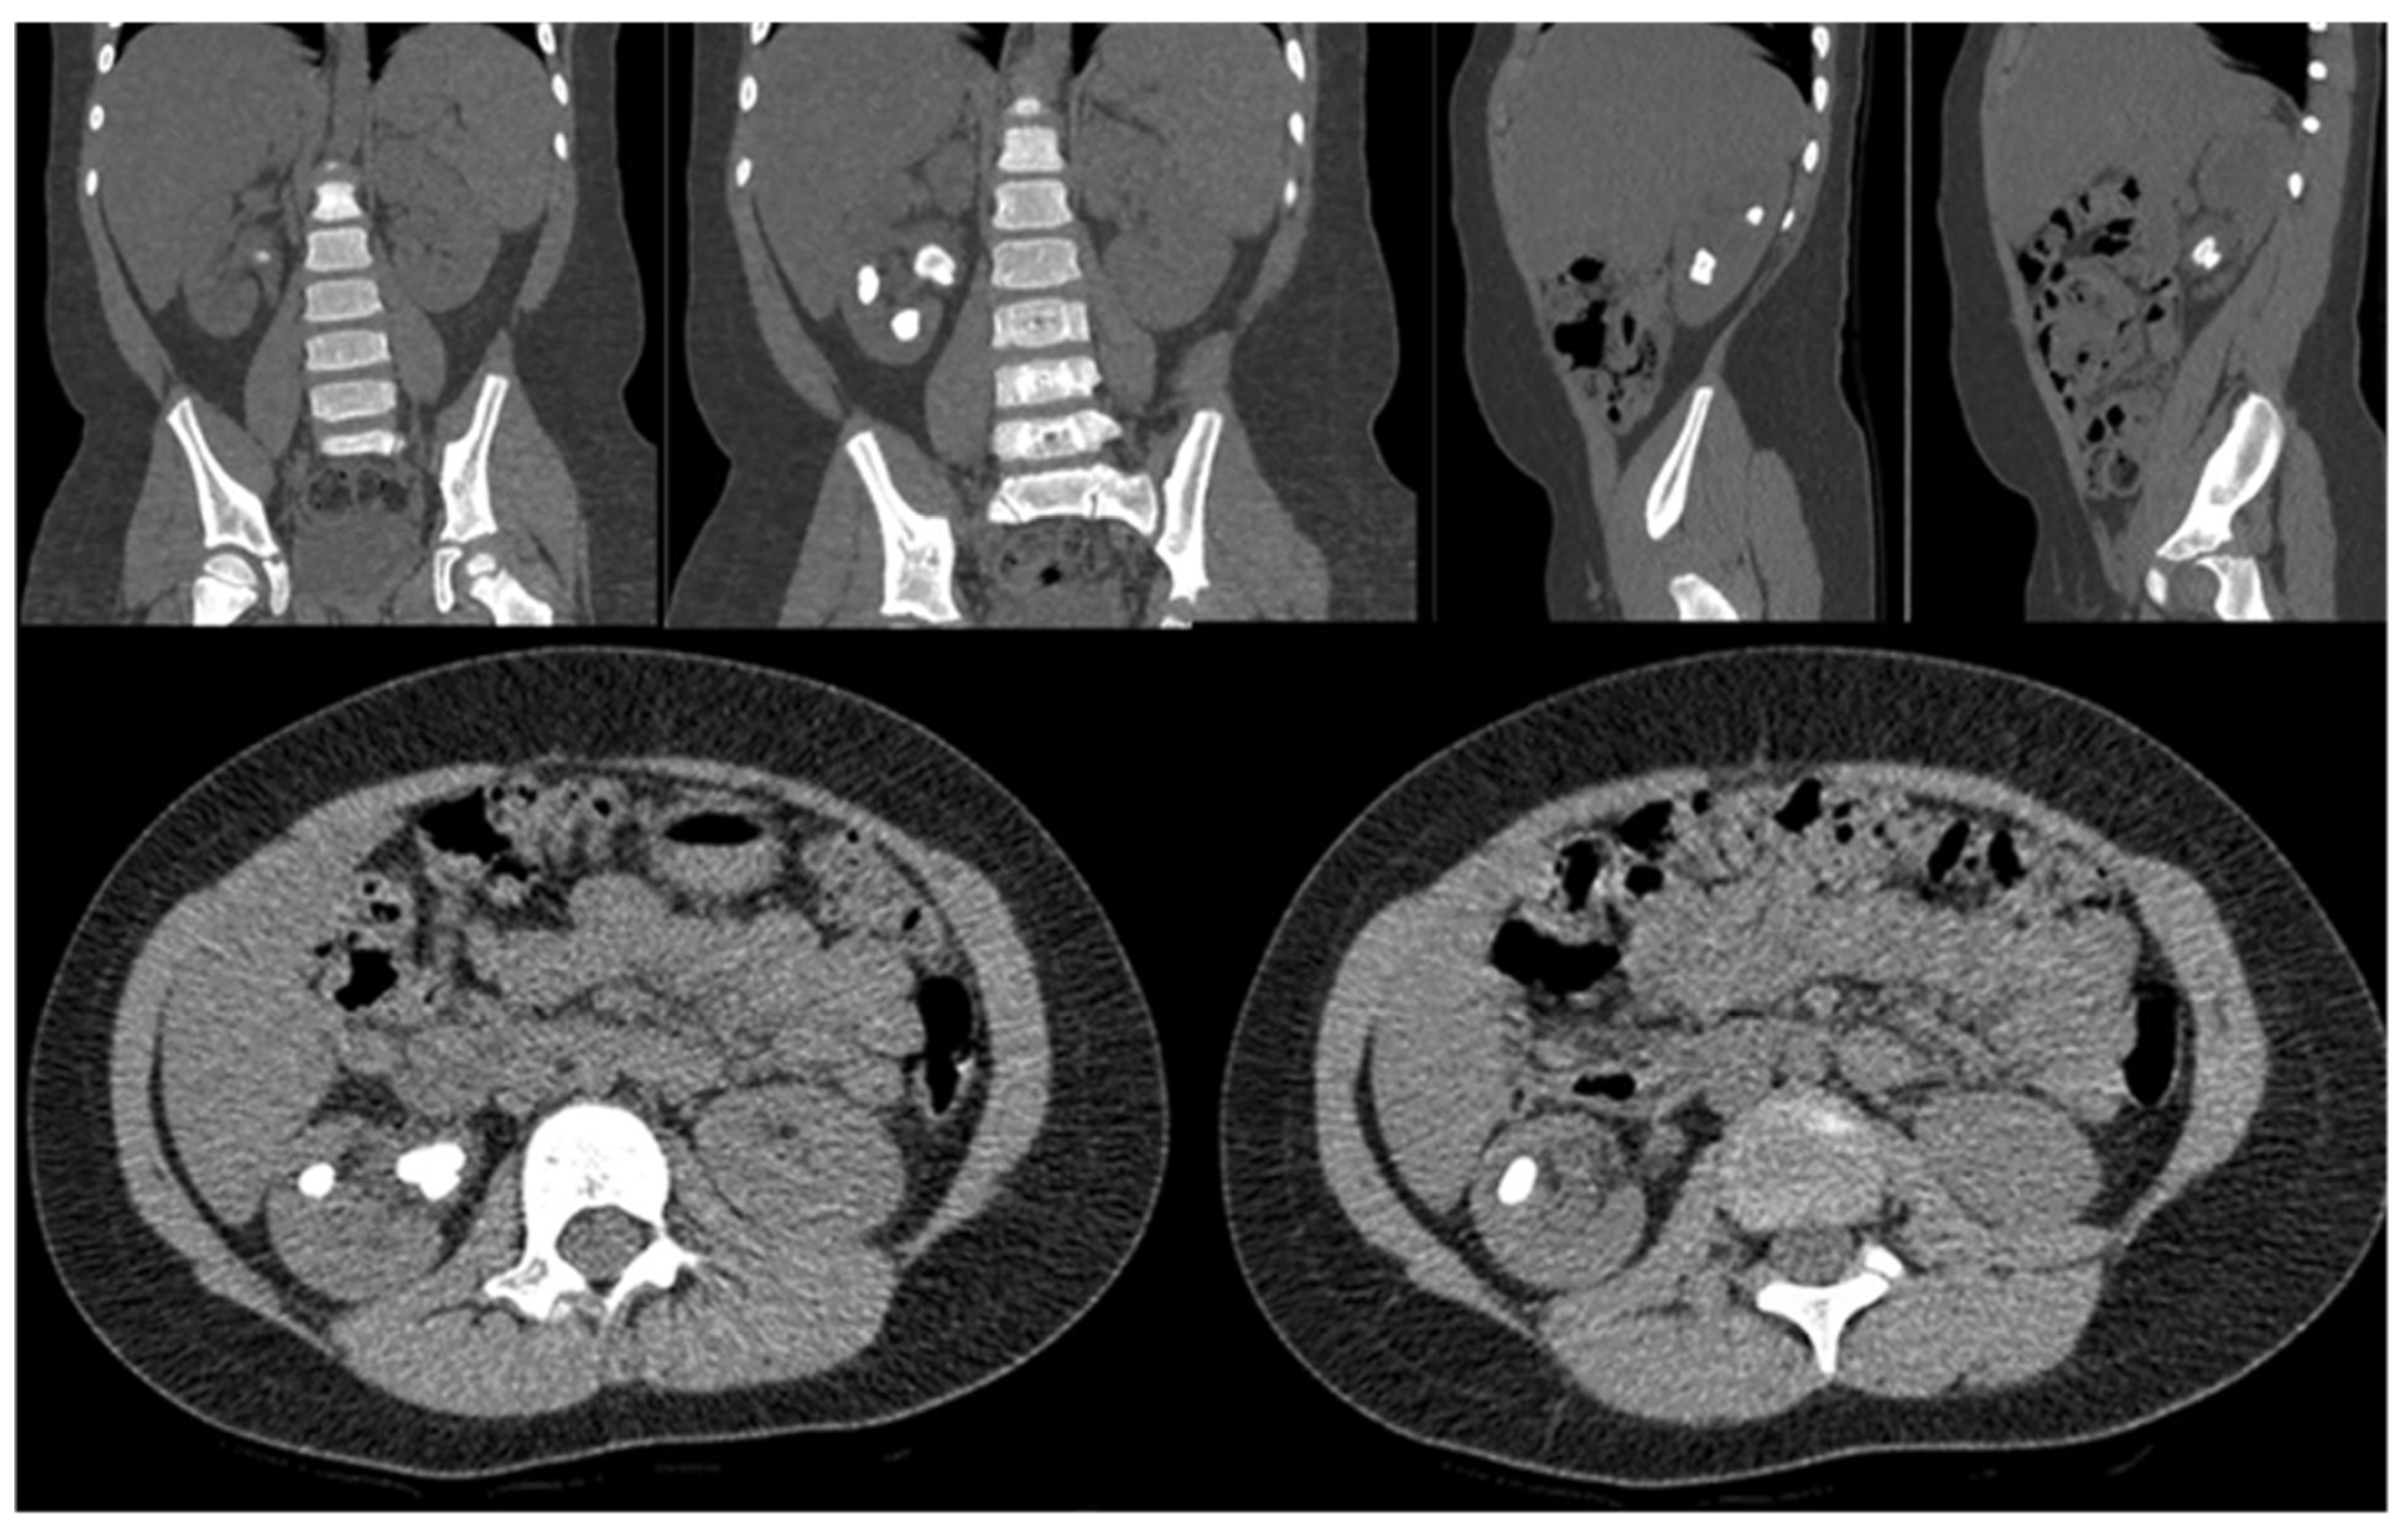

| Associated renal anomalies |